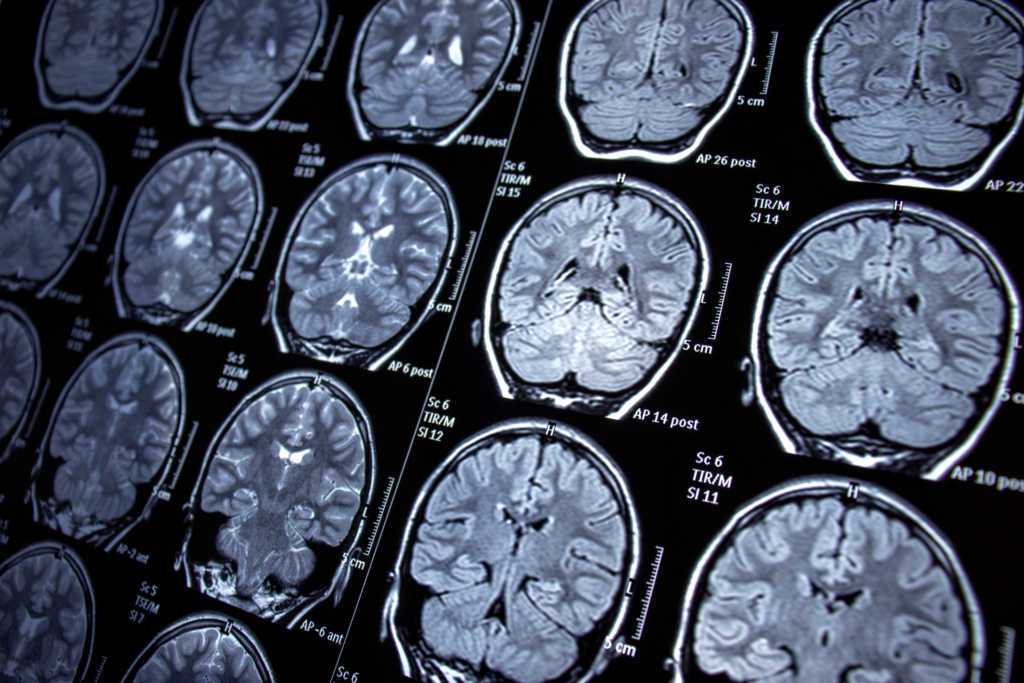

Mutations in the GNAO1 gene of the G203R variant are the most aggressive form of the disease. Patients diagnosed with this variant experience the full spectrum of symptoms associated with the disease: from seizures to movement disorders of different types.